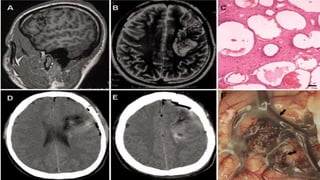

ARTERIOVENOUS MALFORMATIONS

• AVM is an abnormal tangle of blood vessels connecting arteries and veins,

which disrupts normal blood flow and oxygen circulation.

• AVMs may be small and focal, or they may be large, involving an entire

hemisphere. Some are conical, with the apex pointing inward and the base

positioned on the surface of the cerebral cortex. In rare instances, the lesion

is so deep that the ventricles and choroid plexus are involved, thus

predisposing the person to intraventricular hemorrhage.

CAVERNOUS MALFORMATIONS

• Also called cavernous hemangiomas, cavernous

angiomas, and cavernomas, are congenital

nodular lesions.

• They resemble a mulberry or “popcorn-like”

appearing lesion in the brain, spinal cord, or

nerve roots and are composed of sinusoidal-

type vessels that are not separated by normal-

appearing parenchyma (neural tissue).

• Microscopic examination often reveals

small haemorrhages with numerous,

hemosiderin-laden macrophages and

gliotic tissue in the adjacent

parenchyma. Elastic fibres are absent in

the walls of these vascular caverns.

Thrombosis may be present in some of

the dilated venules. Calcification within

the lesion is common.